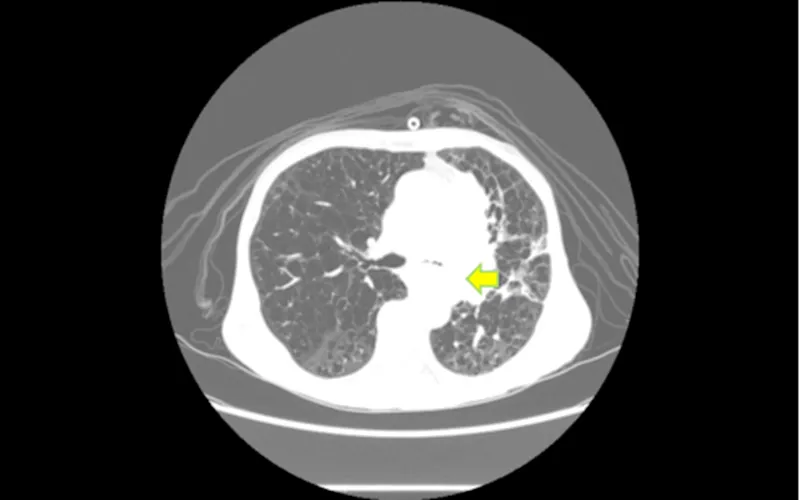

▲左肺门-纵隔肿块(黄色标记狭窄区域)

术中发现左主支气管黏膜严重肿胀、增粗,左肺上叶支气管被新生物完全堵塞,左肺下叶支气管极重度狭窄。手术团队运用激光技术成功消融了管腔内的新生物,扩大了左肺下叶支气管管腔,使得4.2mm的气管镜能够自由通过,有效缓解了患者的气道阻塞症状。